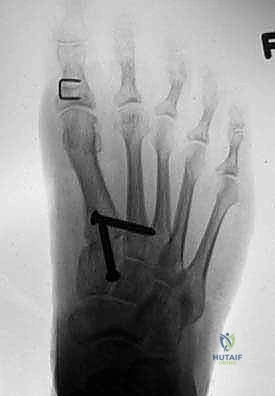

- الأشعة السينية مع تحمل الوزن (Weight-bearing X-rays): صور من الأمام، الجانب، والزوايا المائلة لتقييم زوايا العظام تحت تأثير وزن الجسم.

- تصوير السمسمانيات (Sesamoid view): لمعرفة ما إذا كانت العظام السمسمانية قد خُلعت من مكانها.

أ. إعادة القطع العظمي (Revision Osteotomy - Scarf or Chevron)

إذا كان الفشل ناتجًا عن تصحيح غير كافٍ في الجراحة الأولى، وكان المفصل لا يزال سليمًا (لا توجد خشونة شديدة)، يقوم الدكتور هطيف بإجراء قطع عظمي جديد (مثل تقنية Scarf أو Chevron) لإعادة توجيه العظم وتثبيته بمسامير تيتانيوم حديثة لا تسبب تهيجًا.

ب. عملية لابيدوس (Lapidus Procedure - TMTJ Arthrodesis)

إذا كان سبب التكرار هو "فرط الحركة" في مفصل منتصف القدم (TMTJ)، فإن الحل الوحيد لمنع التكرار المستقبلي هو دمج (إيثاق) هذا المفصل. يزيل الدكتور هطيف الغضروف من المفصل، يصحح زاوية العظم، ويثبته بشريحة معدنية قوية ومسامير حتى يلتحم العظمان معًا. هذه العملية تعالج أصل المشكلة من الجذور.